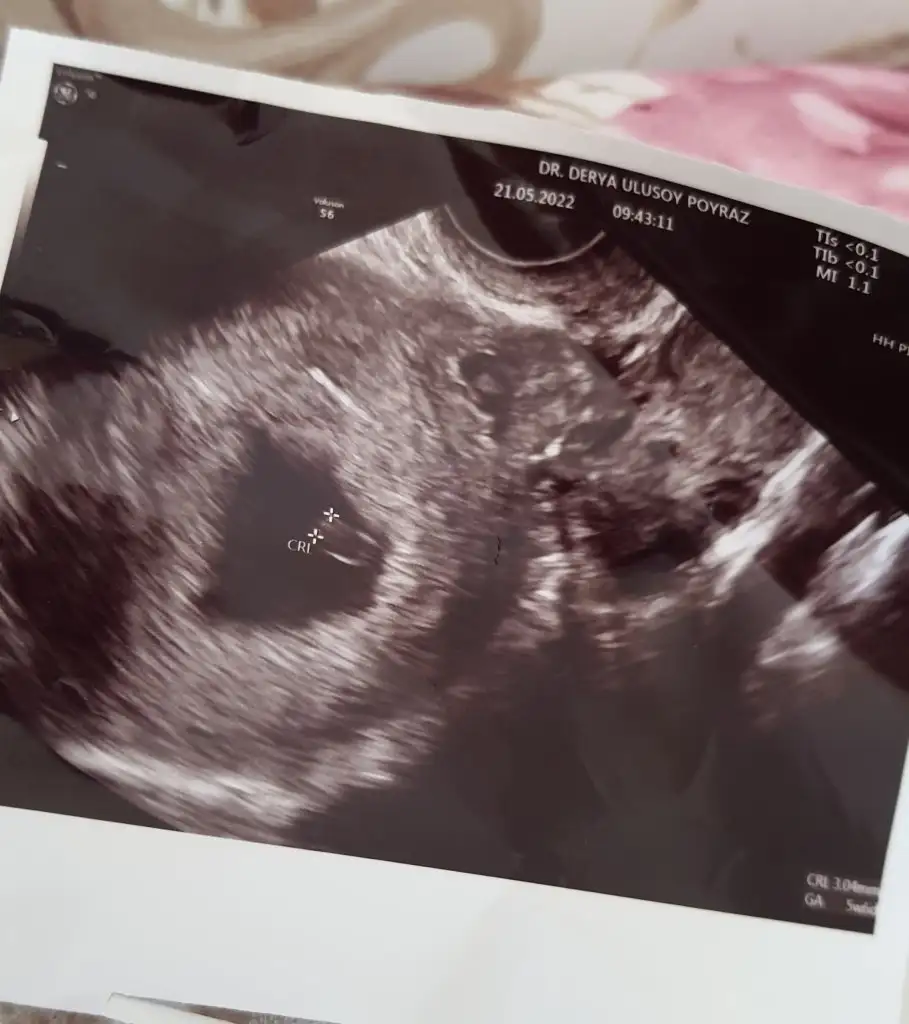

Ramzi teorisine göre cinsiyet tahmini yapacagim ilk ultrasyon resminizi atin bakiyim. Eger cinsiyetiniz belliyse hic söylemeeyin bakalm dogru tahmin edebilecekmiyim daha dogrusu ramzi teorisi hakli cikacak mi?